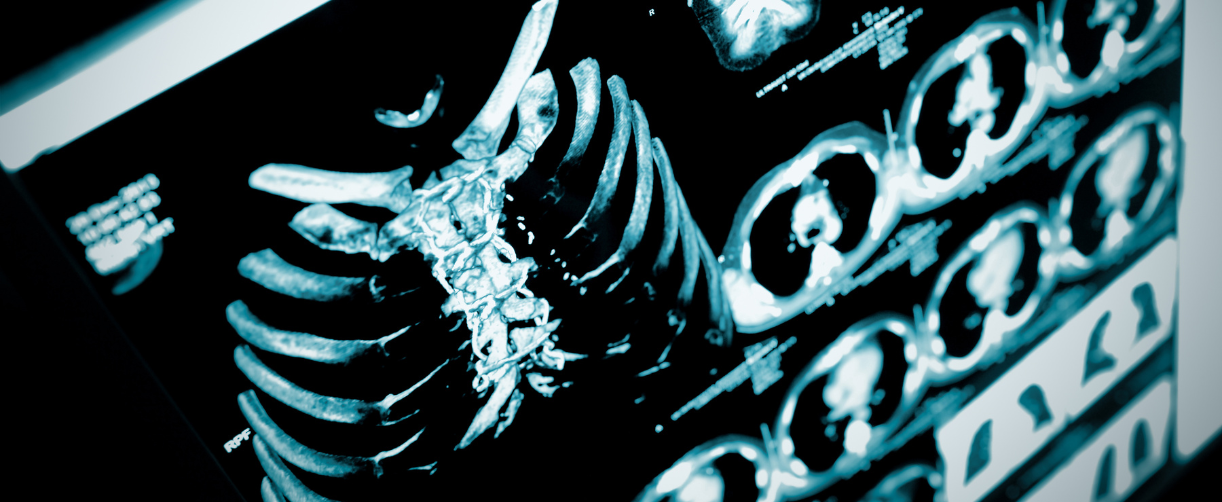

Can New Tech Help us Diagnose Rib Tumours More Effectively?

Technology is changing the way we detect and treat health conditions, especially when it comes to rare or hard-to-spot diseases. In the case of rib fibrous dysplasia—a type of benign bone lesion that can be difficult to identify—advanced imaging tools are offering doctors clearer insights. Traditional scans don’t always give a full picture, especially when tumours have unusual shapes or mimic other conditions, but with CT 3D reconstruction, doctors can now view high-resolution, three-dimensional models of the ribs, making it easier to see the tumour’s size, shape, and position. Artificial intelligence also plays a key role, boosting speed and accuracy by using smart algorithms to spot abnormalities that might otherwise go unnoticed.

This case report from Dubai Medical Journal explores how combining these two technologies improves diagnosis and supports better planning and personalised care for patients.